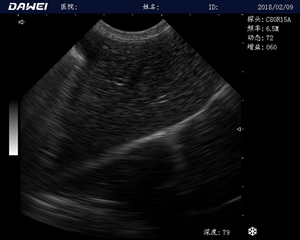

MT15獸用B超機適用探頭

適用對象:

牛羊馬豬犬貓及多種家禽、實驗動物、野生動物、及部分水生動物

應(yīng)用范圍:

中小動物的肝、膽,脾、腎、膀胱、子宮、妊娠等各組織器官的檢查和病變的診斷